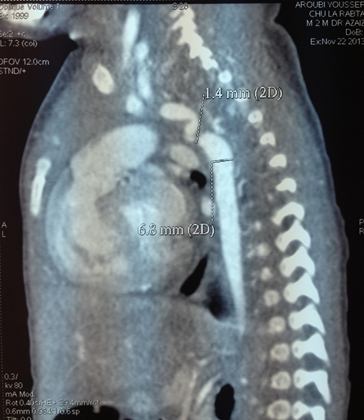

A 57-day-old male infant was referred to our department for management of dyspnea. He was born by normal vaginal delivery to parents of first degree consanguineous marriage. The pregnancy was uneventful and prenatal ultrasounds were normal. Mother was a 32-year-old primigravida. Apgar scores were of 9 and 10 at the 1st and 5th minutes, respectively. His birth weight was 3150g (75th percentile). He had a normal physical examination at birth. At 55th day of life, the baby presented with dyspnea with feeding difficulties and was admitted to our department. On examination, weight was 3770g, he was hypothermic, had respiratory distress with tachypnea and retraction signs. The extremities were cold. He was cyanotic with oxygen saturation at 85% in the air. Cardiac auscultation revealed a gallop and single 2nd heart sound. There was hepatomegaly. Femoral pulses were not found though axillary pulses were present suggesting aortic coarctation. Blood pressure was 125/80 mm of Hg in the upper extremities and 90/50 in the legs. On chest X-ray there was cardiomegaly, hepatomegaly and increased pulmonary vascular markings. Electrocardiogram (ECG) showed left ventricular hypertrophy. 2-D transthoracic echocardiogram (2D Echo) showed tightly bound isthmic coarctation of the aorta with a small aortic arch and a pre structural patent ductus arteriosus shunting exclusively the aorta and pulmonary artery with a flow of 4m s-1. There was a severe congenital mitral stenosis with the gradient between the left auricle and the left ventricle at 8 mmHg. Aortic valve was bicuspid with aortic stenosis. There was a left ventricular hypertrophy. The maximum gradient between the left ventricle and the aorta was estimated to be 19 mmHg. This gradient was underestimated because of the coarctation of the aorta. The pulmonary arterial pressures were normal. Computed tomography angiography showed aortic coarctation and left ventricle hypertrophy (Figure 1). He was treated with oxygen, furosemide, alprostadil and surgical coarctation repair was performed on the 60th day of life. Correction of mitral stenosis will be planned for the future. The postoperative course was uneventful.

Figure 1: Computed tomography angiography showing aortic coarctation